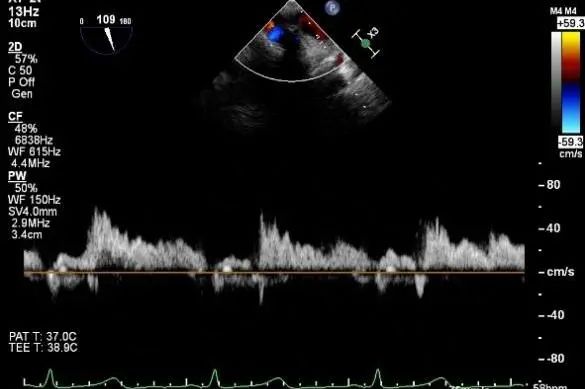

肺静脉多普勒收缩期反向血流

麻醉状态下TEE显示中大量返流MR:

术后肺静脉频谱